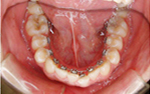

全て乳歯です。反対咬合です。まだ幼児なので、お子様にかかる負担などをよく考えた上で、治療します。

反対咬合です。